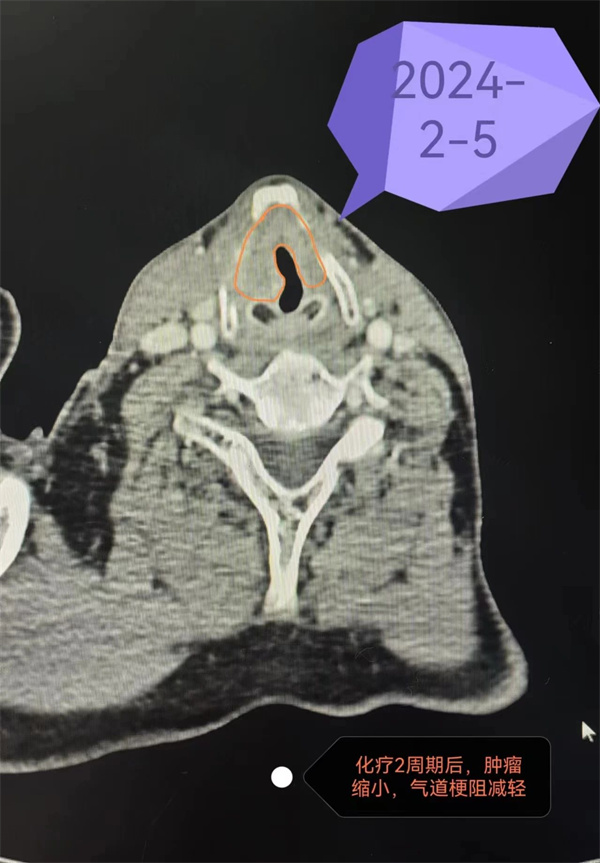

终于,在2024年2月5日的复查中,增强CT检查结果显示肿瘤已经明显缩小,不再影响呼吸。当患者听到他可以拔除气管插管这个消息时,激动得热泪盈眶。是的,这是生命的奇迹,患者也重新找回了自己的声音。